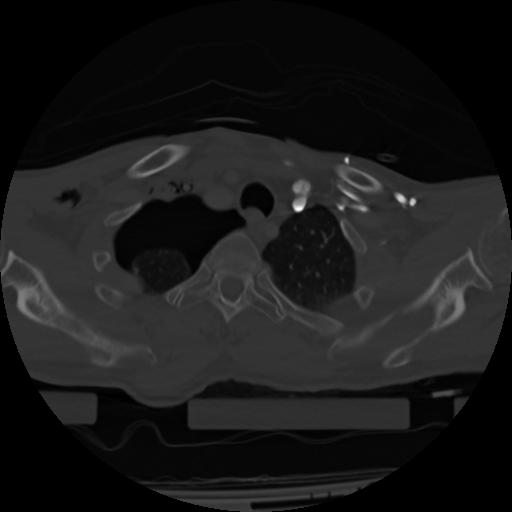

21 ANGIO,CE,Axial,3.0,ANGIO,,